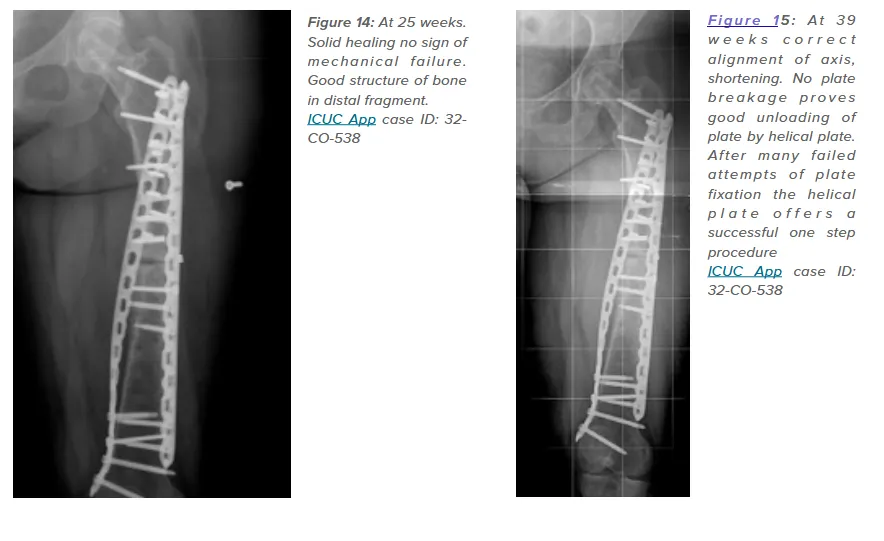

One notable case (ICUC App ID: 32-CO-538) involved a young patient with repeated plate failures for a comminuted femoral shaft fracture. The addition of a helical plate reduced bending loads, resulting in solid healing and no mechanical failure at 25 weeks. This underscores the potential of helical plates to prevent fatigue failures and support early functional recovery.